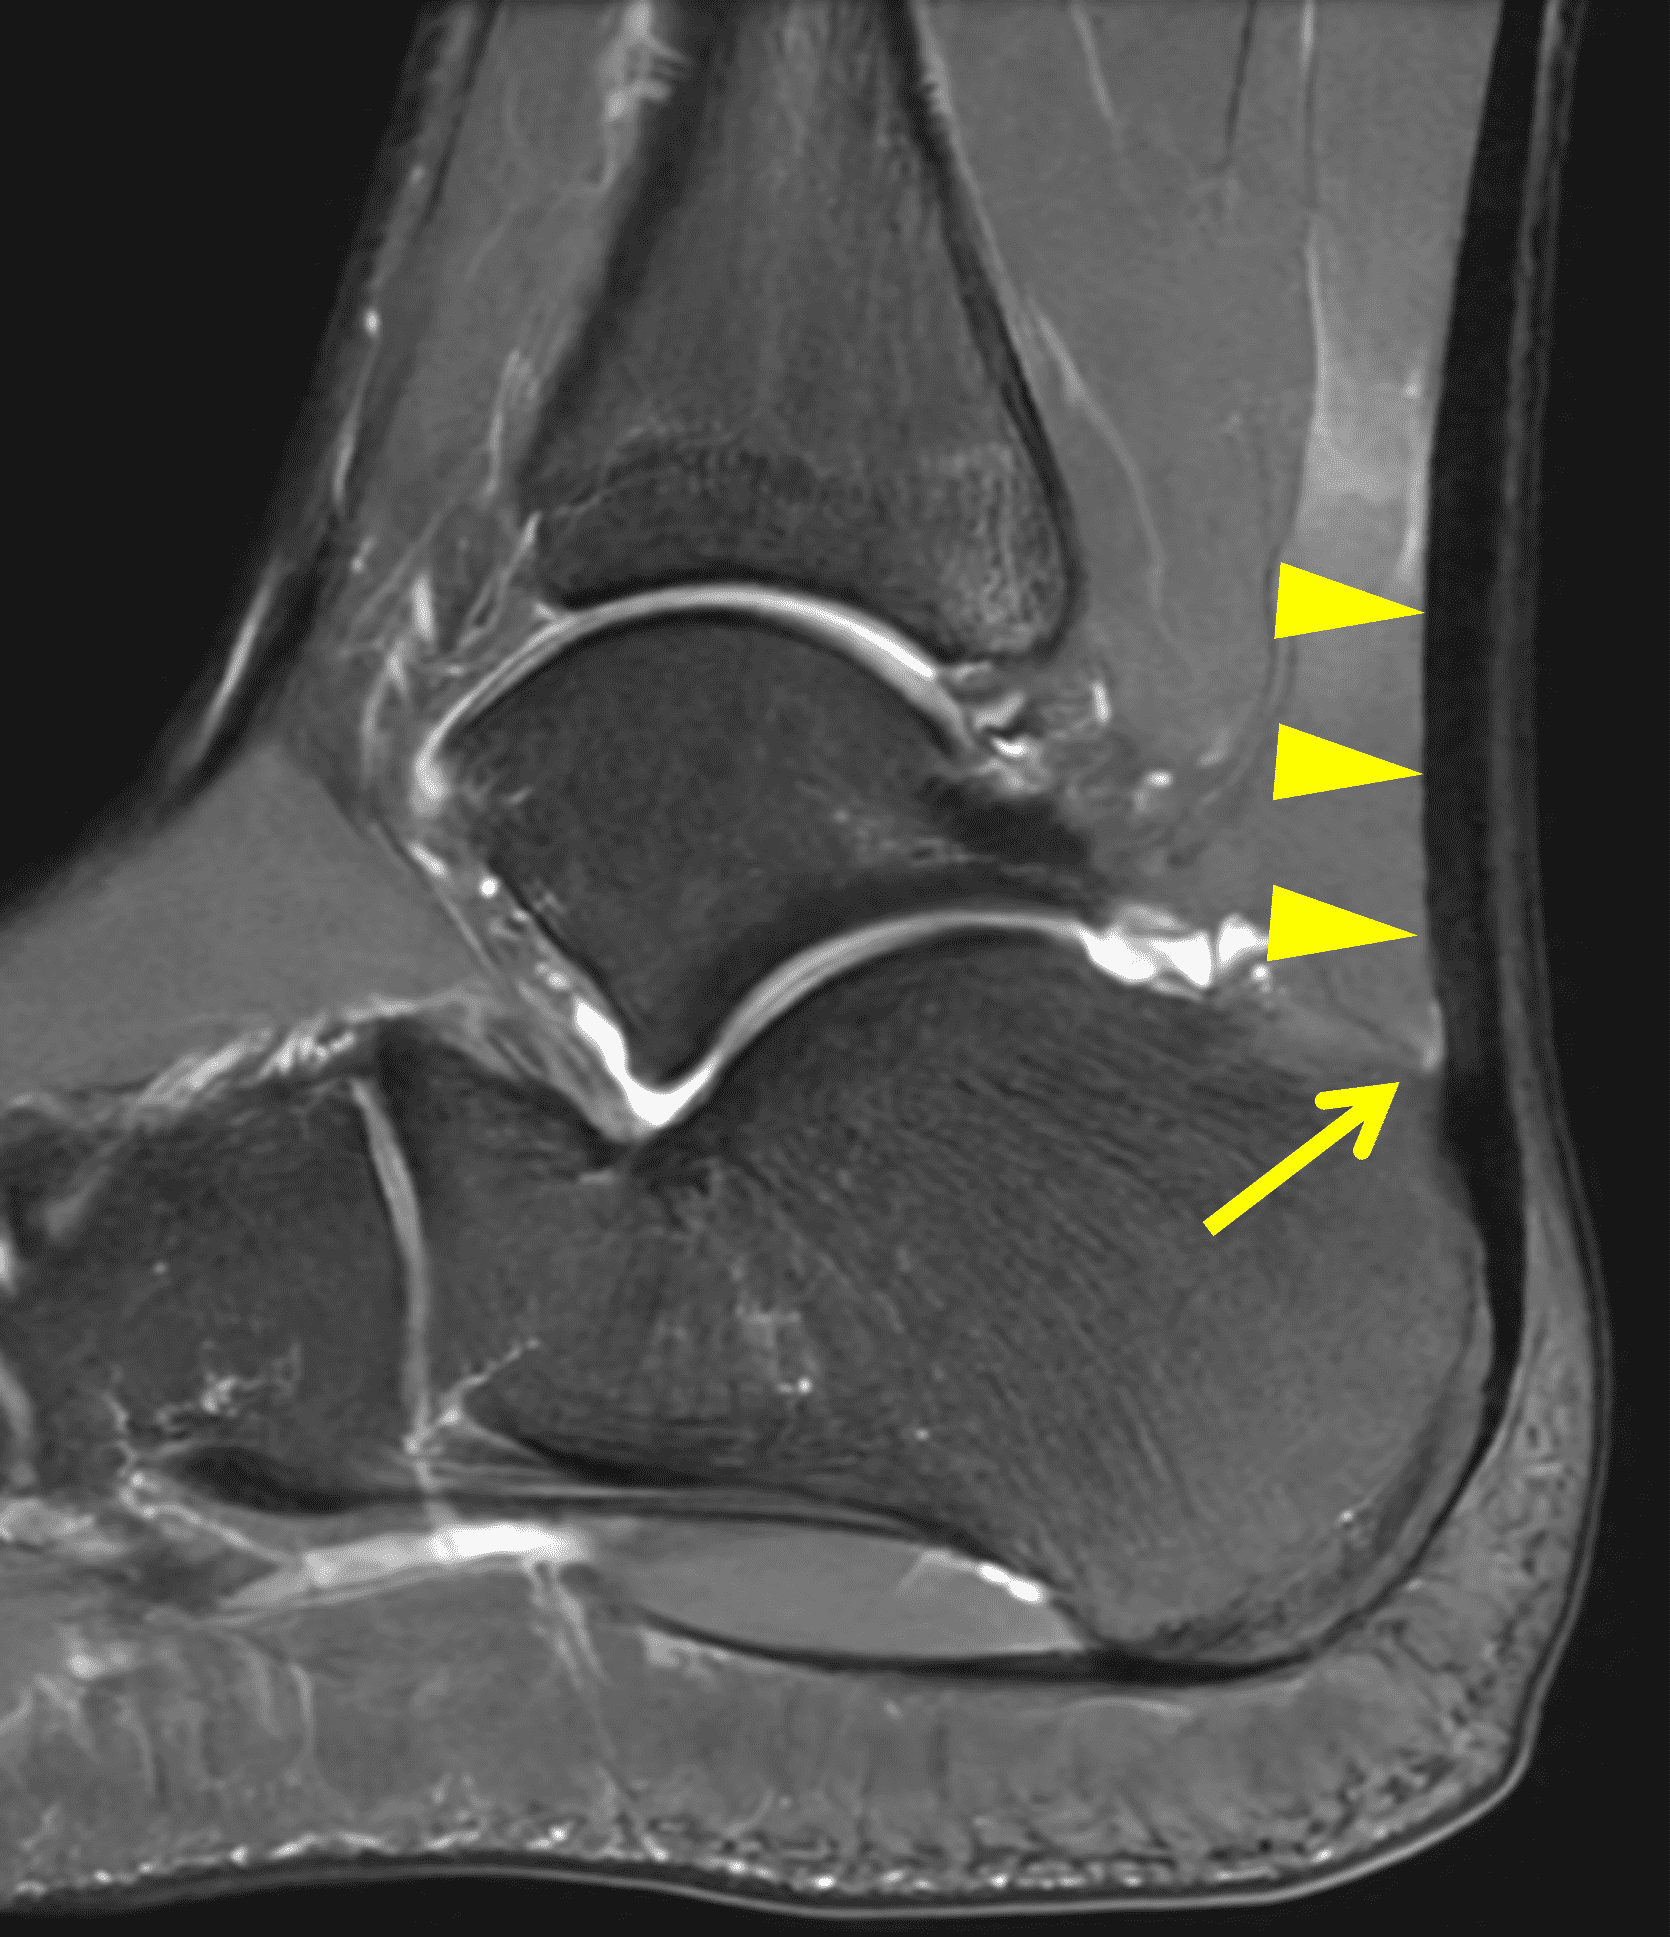

On MR images, the normal Achilles tendon demonstrates low signal intensity on all sequences (Figure 4). On sagittal images, the tendon should be uniform in thickness and have a sharp anterior margin where it abuts Kager’s fat pad. High-resolution images may reveal fine punctate or linear intermediate signal from normal interfascicular septa, especially in the distal tendon, which should not be misinterpreted as tendinosis, particularly when the tendon thickness is normal.6 When the tendon fibers are oriented near to 55° with respect to the B0 magnetic field, increased signal may be seen on short-TE sequences due to the magic angle effect, with decreasing artifact on longer-TE sequences. MR images obtained at higher field strengths (3-7 T) accentuate the fascicular detail and normal septations as well as magic-angle effects.5,6 On transverse images, the posterior tendon margin is typically convex; the anterior margin is flat-to-concave along most of its length but may be focally convex at the gastrocnemius–soleus convergence, which is considered a normal variant. The average tendon thickness is approximately 6 mm, with variation by body size, age, and sex.20

The normal Achilles paratenon appears as a thin low-to-intermediate signal rim.6 The retrocalcaneal bursa lies between the distal tendon and calcaneus and normally contains only minimal fluid. The contents of Kager’s fat pad should be isointense to fat on all pulse sequences, with traversing vessels and thin fascial strands that should not be mistaken for pathology.

Figure 4: MRI appearance of the normal Achilles tendon. (4A) Sagittal T1-weighted image shows the low signal intensity Achilles tendon (t) with uniform thickness. Kager’s fat pad (asterisk) normally contains thin fibrous strands and vessels. S = soleus muscle, F = flexor hallucis longus muscle. (4B) Sagittal fat-suppressed fluid-sensitive sequence shows the sharp anterior tendon margin (arrowheads) and a physiologic amount of fluid in the retrocalcaneal bursa (arrow). (4C) Transverse T1-weighted image just proximal to its insertion shows the Achilles tendon (yellow arrow) with a concave anterior margin and convex posterior margin. The much smaller plantaris tendon (red arrow) lies along the anteromedial margin of the Achilles. (4D) Transverse fat-suppressed T2-weighted image shows punctate foci of higher signal intensity (arrowhead) in the distal tendon representing normal interfascicular septa.